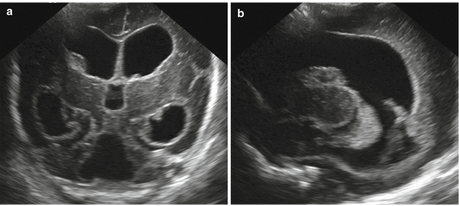

C) Brain Scans: These help doctors understand what kind of brain damage may have occurred.